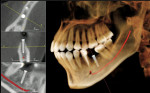

Basic enhancements include zoom or magnification and visual adjustments to narrow the range of the displayed gray scale and contrast levels within the window, as well as cursor-driven measurements and annotations. Third party software programs will provide enhancement features that will allow the image to render with color, highlighting greater detail to the volume. These programs usually have additional functions, such as mandibular nerve location and implant planning (Figure 6).

As with any technology, use of CBCT imaging requires a learning curve that may include education to a higher level of competency in anatomy and radiographic interpretation if reading the images is planned. The American Academy of Oral and Maxillofacial Radiology has stated that CT and implant imaging should be performed only by a board-certified oral and maxillofacial radiologist or a dentist with adequate training or experience.37 In most states, there are oral and maxillofacial radiologists willing to provide the service of reading the image volume and sending the general dentist a report. The authors strongly recommend this service with any volume that shows anatomy other than dentition. The time saved by using such a service allows the dentist to concentrate on clinical dentistry.